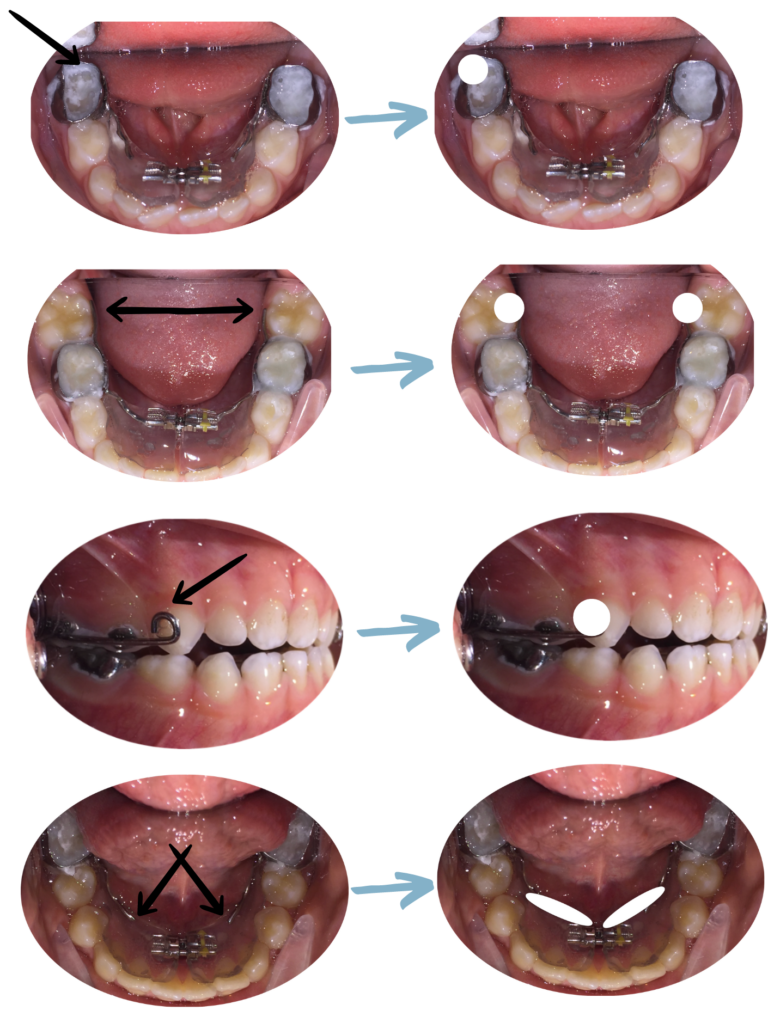

4. Caiguda de l’aparell

El ciment utilizat per enganxar l’aparell és de molt alta qualitat, no obstant en ocasions l’aparell es pot desenganxar per diferents motius que no sempre aconseguim esbrinar (estrabada de l’aparell amb els cabells, una peça de troba, aplicació de forces repetitives amb la llengua o amb els dits, infiltració de saliva durant la col·locació, inflamació de la geniva…)

– Si l’aparell ha caigut completament –> envieu-nos un email + foto de l’aparell a: pacients@ipocubric.com

– Si l’aparell s’ha desenganxat només d’una banda:

1. intenteu treure’l sencer també del costat que no s’ha desenganxat, si no ho aconseguiu, torneu-lo a encaixar i vigileu que no el mossega

2. envieu-nos un email + foto de l’aparell a: pacients@ipocubric.com

Aparell caigut completament

Aparell desenganxat

7. Traumatisme a la zona orofacial (accidents domèstics)

– Les caigudes i cops sobre les dents, barbeta, llavis i zona orofacial en general, són freqüents en els nens.

Aquests traumatismes pràcticament mai afecten els aparells, ja que els aparells es troben dins la boca i estan protegits.

– Quan hi ha un traumatisme sobre una dent, és imprescindible agafar hora de visita amb un especialista en odontopediatria. NOSALTRES NO SOM ODONTOPEDIATRES I NO TENIM CAPACITAT PER A FER AQUEST TIPUS DE CONTROL.

– Per a verificar que el cop no ha afectat l’aparell: envieu-nos un email + foto de l’aparell i la zona traumatitzada a: pacients@ipocubric.com

A continuació, explemes de traumatismes sense afectació dels aparells: